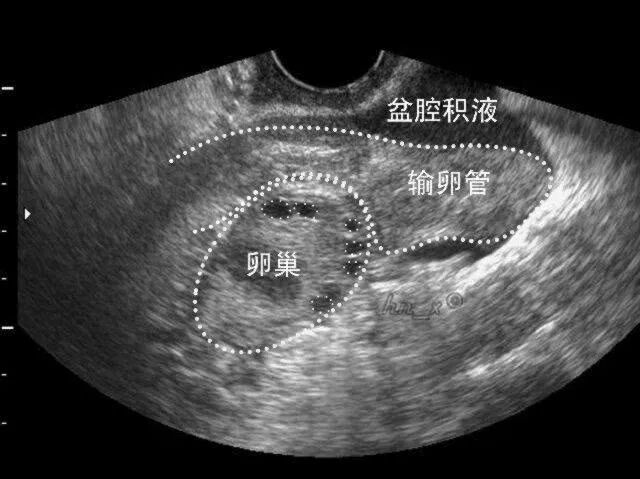

人体的盆腔、腹腔并不是干巴巴的,盆腹腔内腹膜、大网膜、肠管等都会分泌一些液体,这些液体通常起到润滑和保护盆腹腔器官和组织的作用。它们在不停的分泌这些液体,也在不停的吸收这些液体。人体在站立时,盆腔在人体内相对位置较低,这些分泌的液体会积存在盆腔最低处,即子宫和直肠陷凹处。此时借助超声,可以观察到该凹陷内有一定深度的液性暗区,就是“盆腔积液”。

首先需要明确的是盆腔积液不是一种疾病,而是一种临床表现,确切的说是彩超对盆腔内液体的一种描述,分为正常的盆腔积液(生理性盆腔积液)和病理性盆腔积液。正常人体的盆腔积液是生理性盆腔积液,积液量一般是200ml左右。

盆腔积液可通过超声检查观察到,如果积液深度小于3cm,并且没有其他不舒服的症状,通常是不需要处理的。即使积液深度略大于3cm,应结合患者病史、月经期、排卵期、黄体期以及伴随症状(如腹痛程度),排除病理性盆腔积液可能,也不需要治疗。